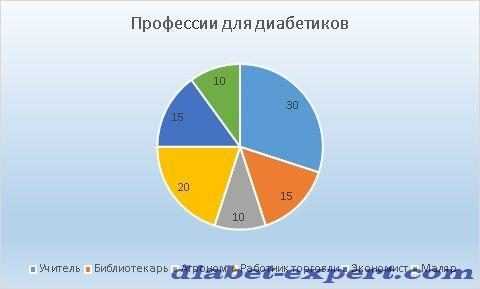

Профессиональная деятельность

Медики рекомендуют выбирать профессию, не требующую резкую смену физических и интеллектуальных нагрузок. У больного диабетом должна быть возможность ввести очередную дозу инсулина или съесть по времени нужную пищу.

Куда идти работать?

На диаграмме указано (в %), какие профессии выбирают молодые люди, страдающие диабетом 1 типа.